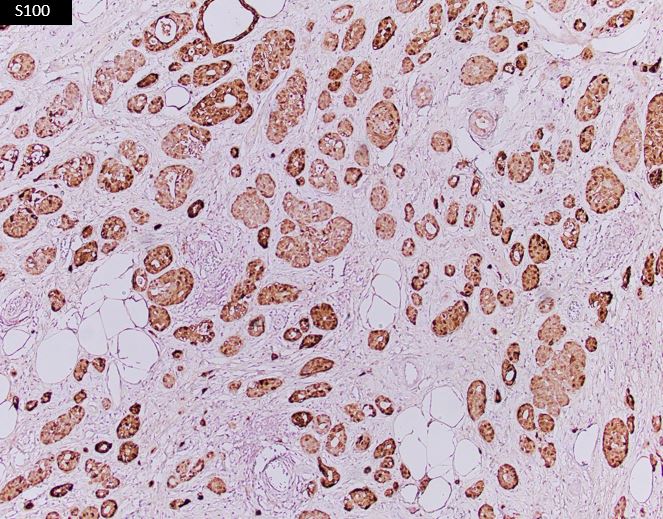

A 75-year-old woman presents with a 3 cm breast mass, undergoes lumpectomy. The neoplastic cells are positive for CK7, S100, and lysozyme.

ACC is characterized by serous acinar differentiation with zymogen-type cytoplasmic granules. The immunohistochemical profile of breast Acinic cell carcinoma shares many features with Acinic cell carcinoma of the salivary glands, with frequent expression of GCDFP-15, S-100, and a-1-Antichymotrypsin, as well as PAS-D positivity.